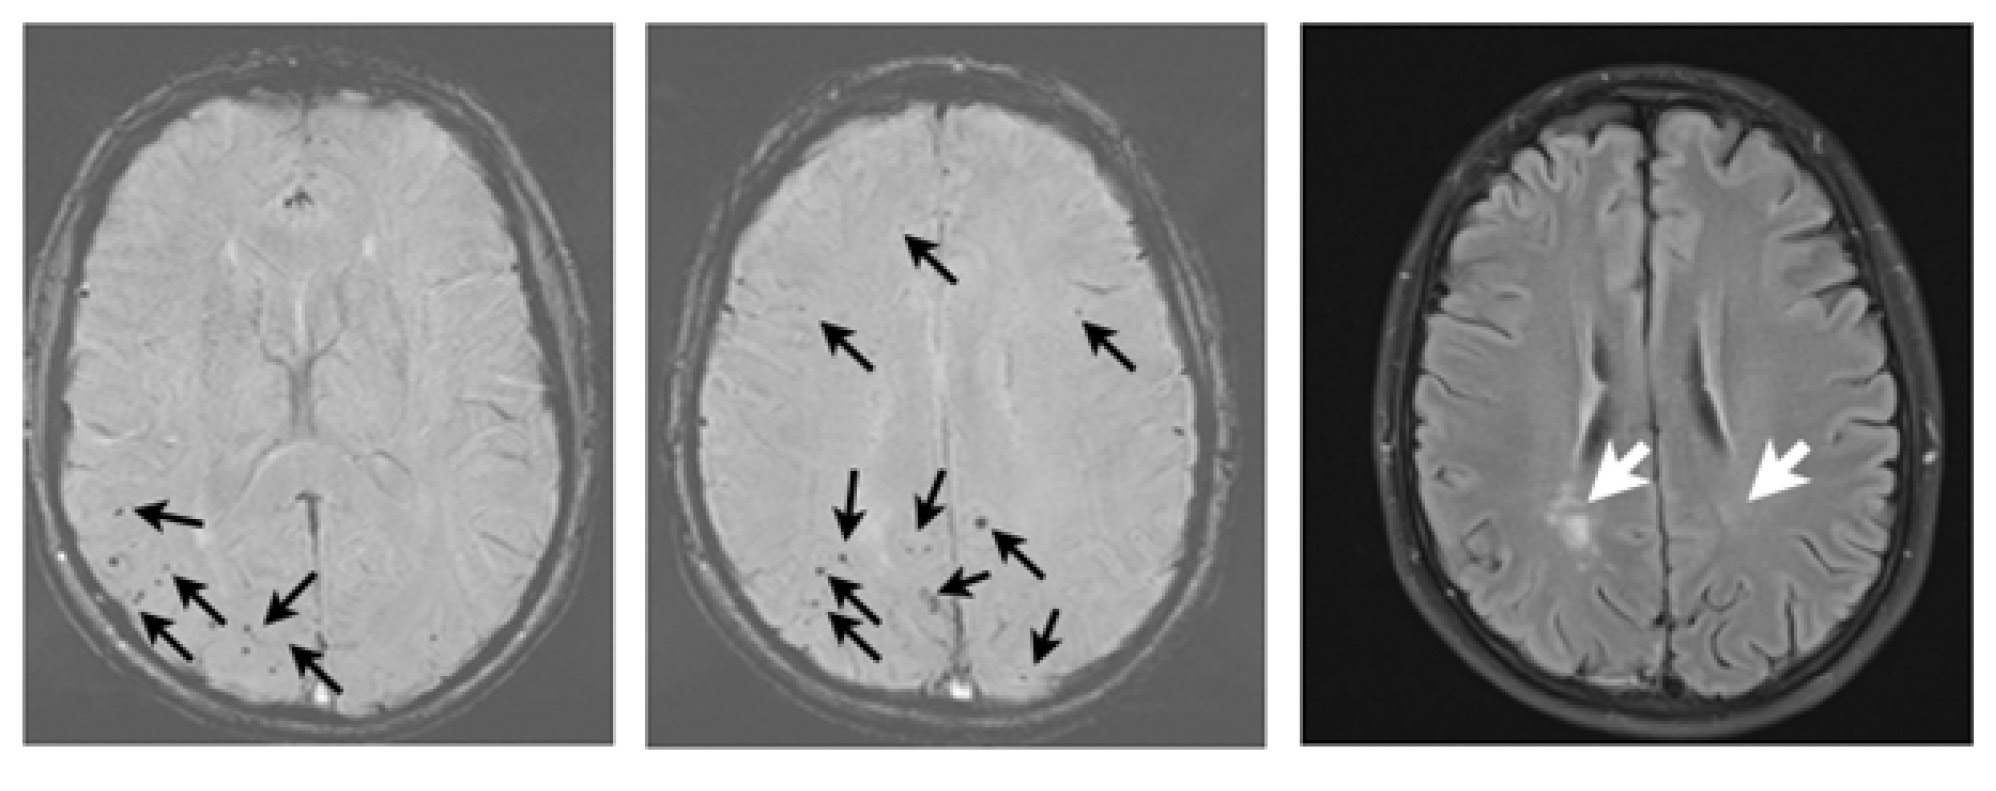

Рис. 2. Результаты магнитно-резонансной томографии головного мозга при повторном обращении в клинику. Представлены результаты исследования в режимах SWI (А) и FLAIR (Б). Стрелками указаны очаги множественных микрокровоизлияний и асимметричные зоны лейкоарайоза

Данные повторной МРТ головного мозга (через 6 мес) представлены на рис. 2. По сравнению с предыдущим исследованием — множественные церебральные микрокровоизлияния без увеличения их количества, зоны лейкоарайоза — с уменьшением в размерах.